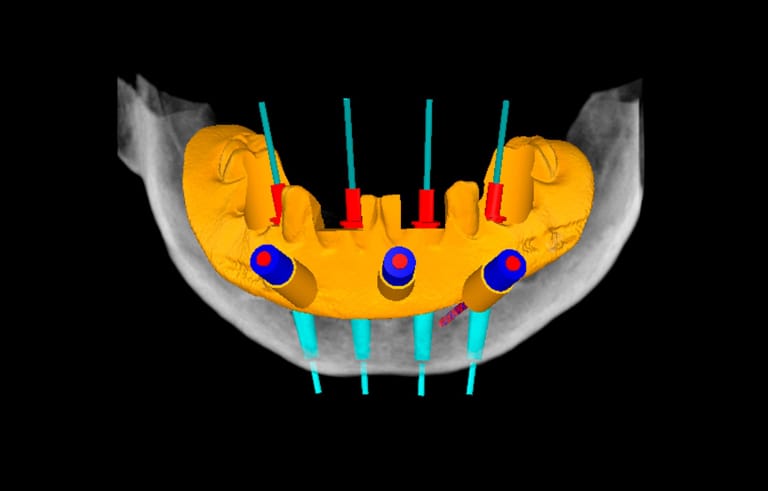

State-of-the-Art Guided Surgery: NavaGation

Surgical guides using CT radiographs and computer-generated imaging are not new in dentistry, but the system we are using from NavaGation takes the process to a new level.

By merging the best CT x-ray technology with sophisticated computer imaging software, we can preplan an implant case, which saves you time in the chair. The system allows for very precise implant placement, which is the key to a great clinical and esthetic result.

We collaborate with your dentist and the dental laboratory to create a surgical guide to ensure that your implants are placed at the correct location, depth, and angle—usually allowing the placement of teeth the same day